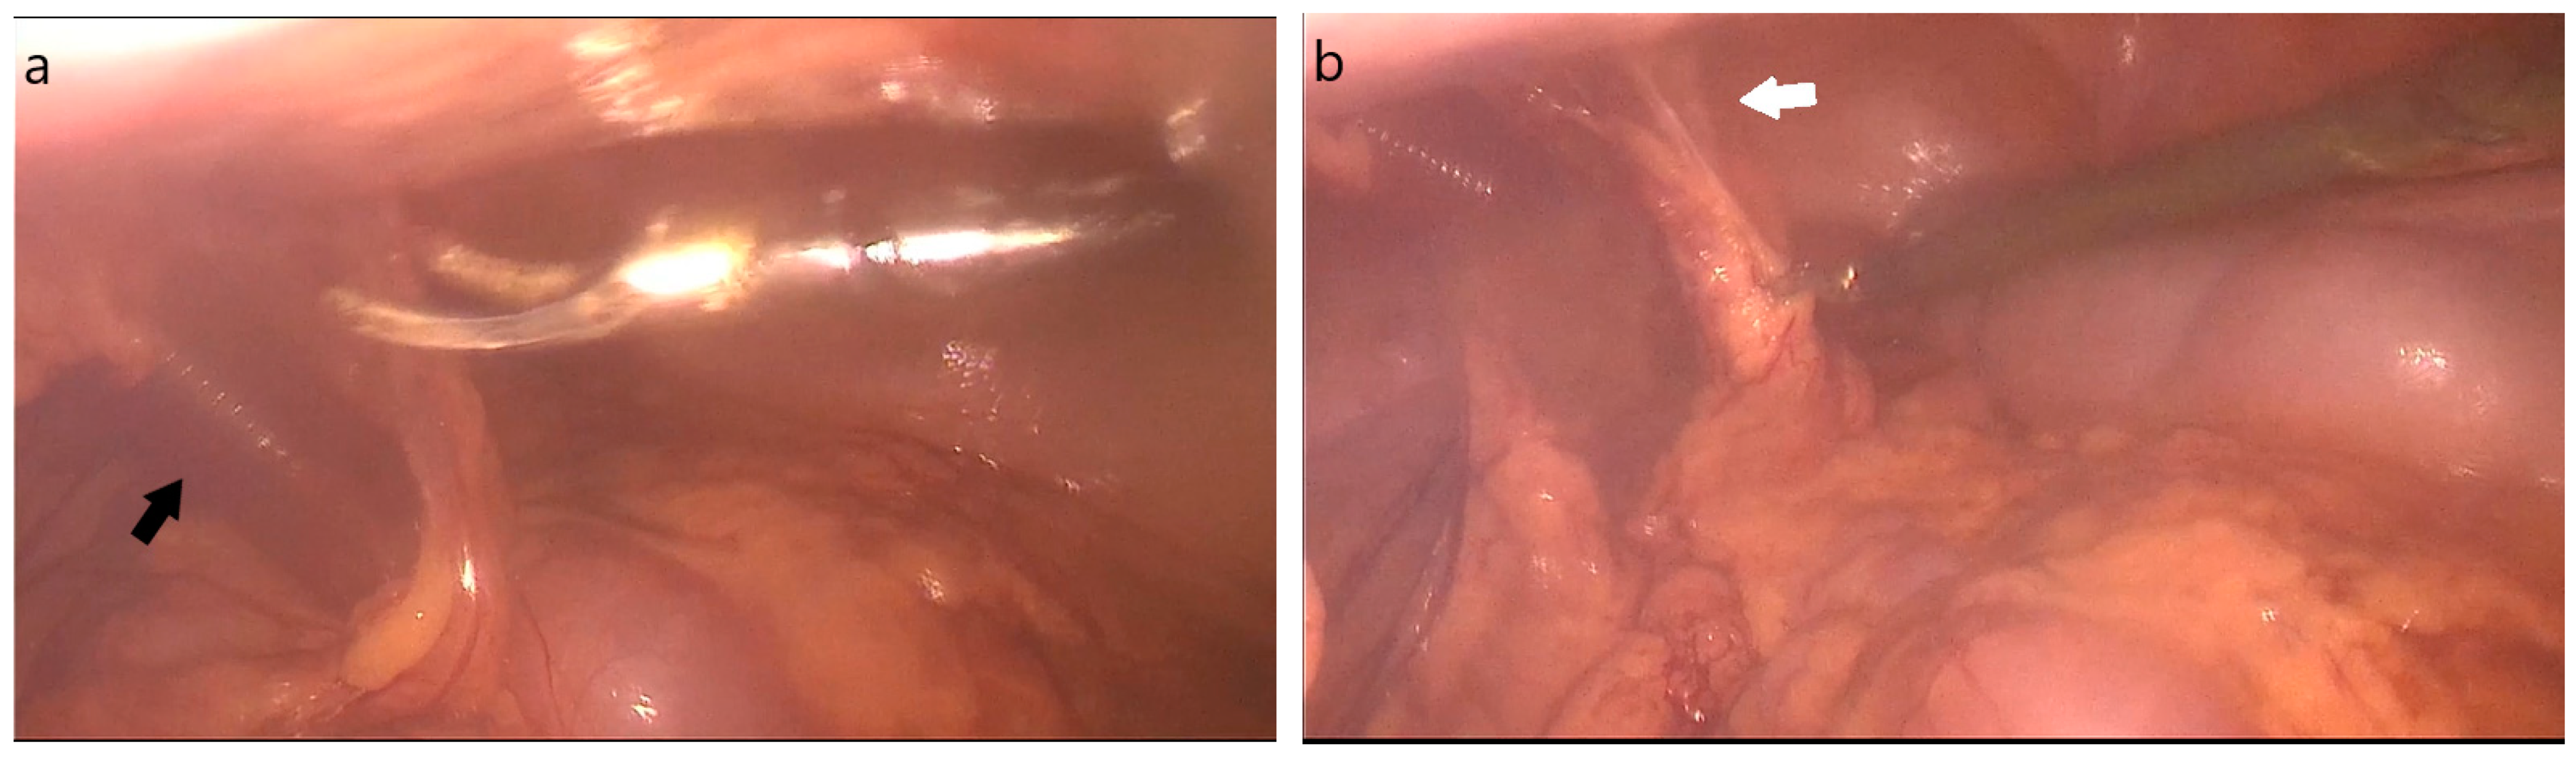

2. Case Description